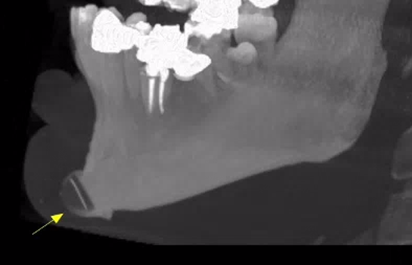

Εκτός από τις παραπάνω ελάχιστα επεμβατικές τεχνικές, στις απεικονίσεις της τραχηλοπροσωπικής χώρας μπορεί να συναντήσουμε και τα αποτελέσματα πιο επεμβατικών τεχνικών, όπως διάφορες μορφές πλαστικής χειρουργικής με χρήση ενθεμάτων σιλικόνης.

Ένα παράδειγμα είναι η γενειοπλαστική, όπως φαίνεται στην παρακάτω περίπτωση.